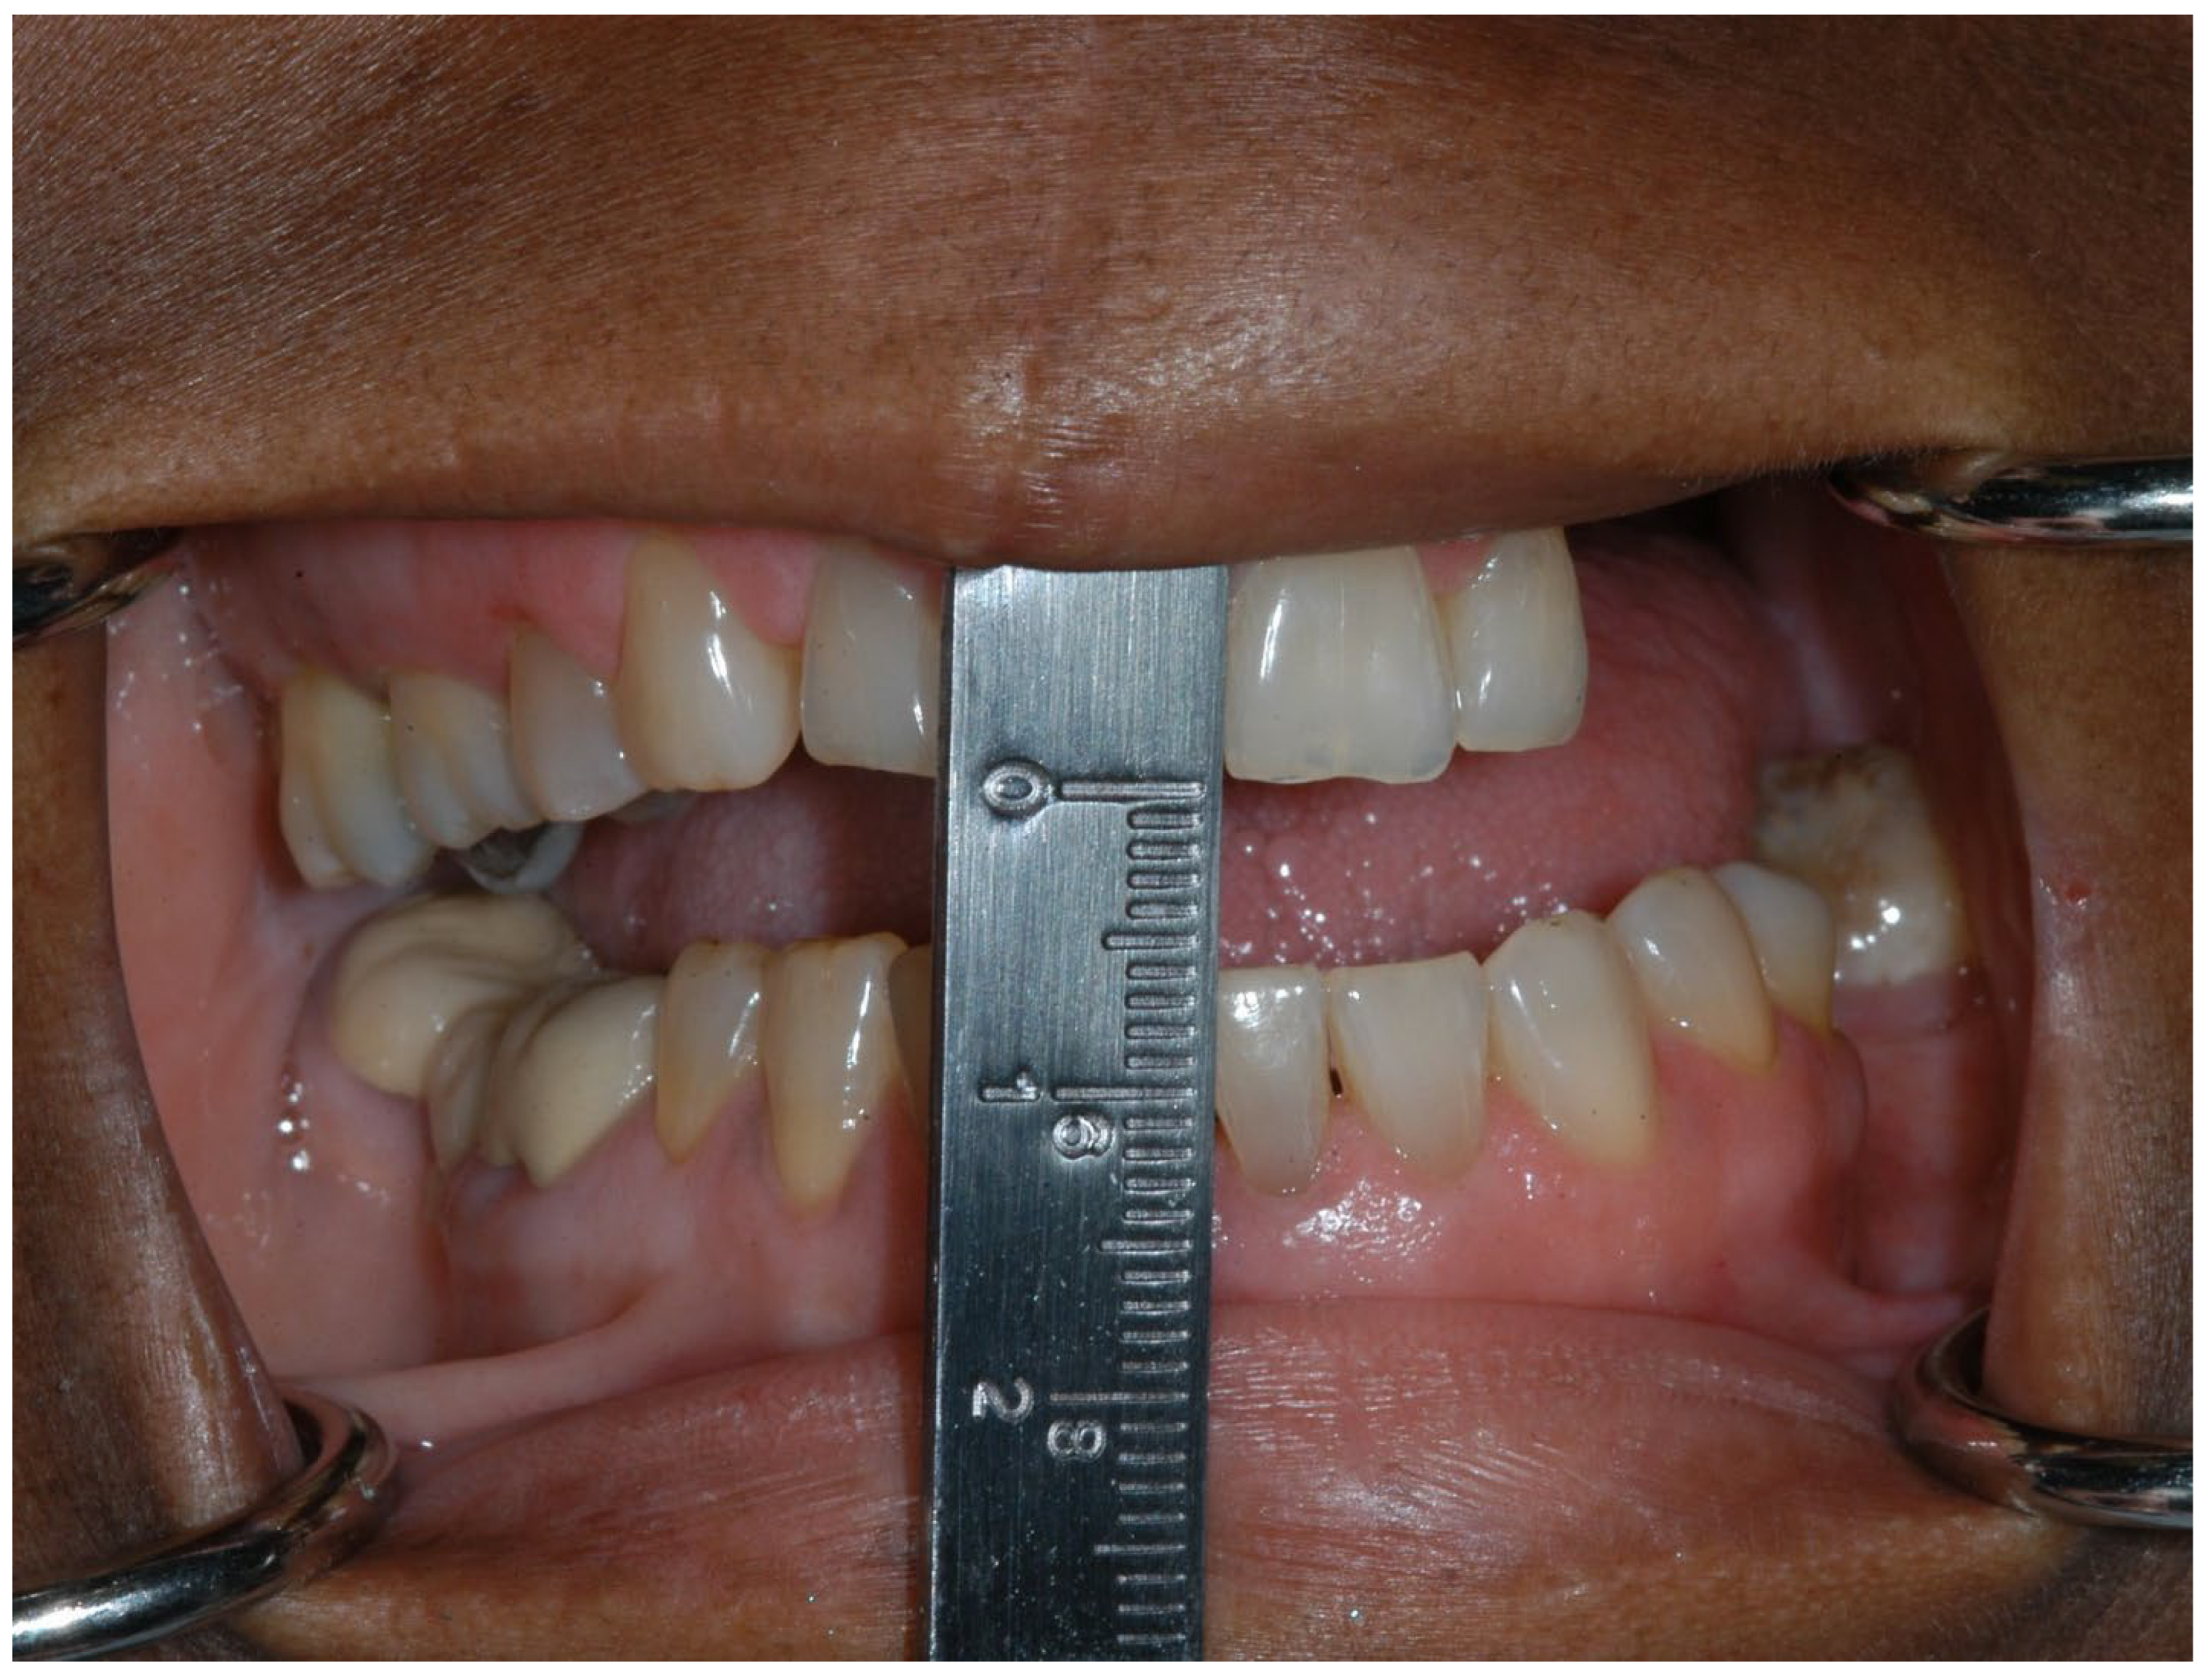

1.2. Trismus

Prevention and Management of Trismus

- Owosho, A.A.; Pedreira Ramalho, L.M.; Rosenberg, H.I.; Yom, S.K.; Drill, E.; Riedel, E.; Tsai, C.J.; Lee, N.Y.; Huryn, J.M.; Estilo, C.L. Objective assessment of trismus in oral and oropharyngeal cancer patients treated with intensity-modulated radiation therapy (IMRT). J. Cranio-Maxillofac. Surg. 2016, 44, 1408–1413. [Google Scholar] [CrossRef]